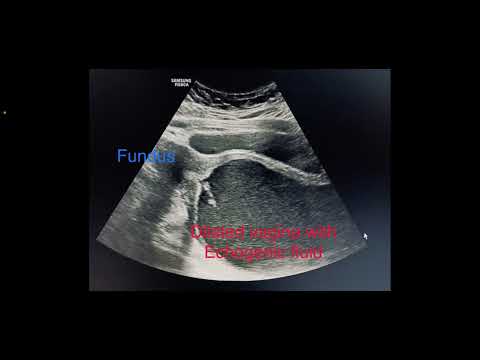

Hematometrocolpos: Imperforate hymen causing severe pain in young female #radiology #ultrasound

Classic case of imperforate hymen with hematocolpos